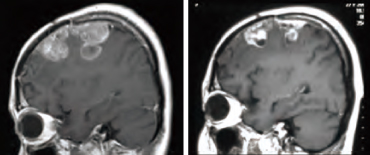

头颈癌(代表案例:复发性腮腺癌)

头颈癌的标准治疗方法是手术、X射线治疗与化疗的联合疗法,但是对复发性头颈癌患者而言,因正常组织对X射线的耐受剂量有限导致头颈癌患者在复发时难以再一次接受X射线治疗。而BNCT可以选择性破坏癌细胞的同时保护正常组织不受损伤,因此在治疗复发性头颈癌方面被寄予了厚望。全球首例针对复发性腮腺癌的头颈癌BNCT在日本关西BNCT共同医疗中心分两次照射实施,其结果癌细胞完全消退,甚至皮表恢复到干性脱屑状态。除了BNCT外,其它治疗手段均不可能避开薄且紧绷的皮肤,对皮下癌细胞直接照射可控剂量,这证明了BNCT是真正意义上的细胞级精度靶向治疗,其优越性不言而喻。

图片

BNCT治疗前

患者因癌细胞的快速生长无法只停留在体内,已突破皮表并呈进一步扩增状态。患者之前做过手术,因此不适合再次进行手术切除,且为放疗后复发病例,也无法再进行包括粒子治疗在内的放射治疗。

BNCT治疗后

癌细胞完全消退,皮肤正在再生中。未观察到对视觉或听觉功能的不良影响。

(图像来源 : 关西BNCT共同医疗中心)